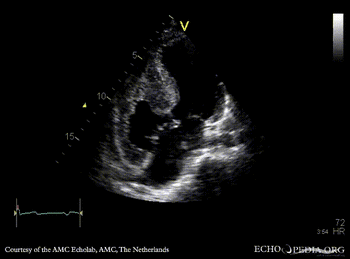

| A4CH: large AVSD